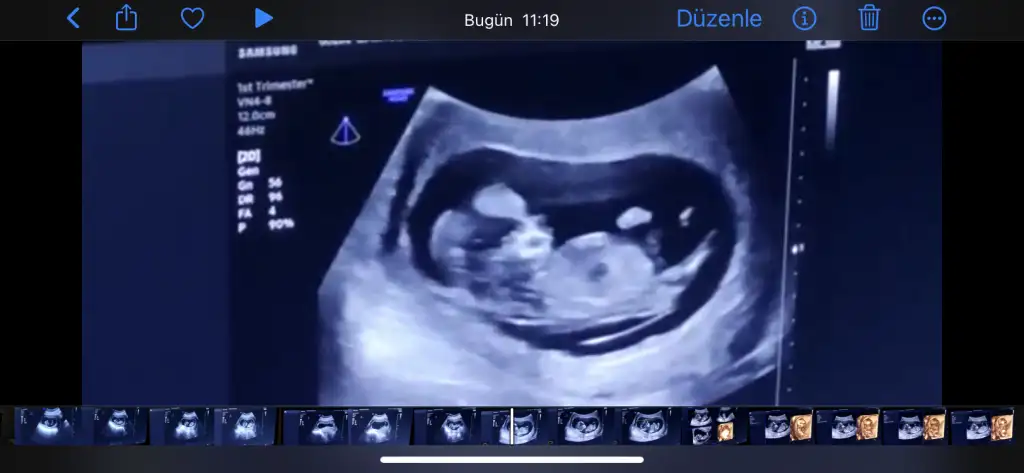

Bu 13+3 te benimkinin nubu. Bacak arasında çıkıntı görülmedi. Doktor kız dedi bana… acaba değişebilir mi diye çekiniyorum …

Çok bi çıkıntı göremiyorum ben canım… nubu belli olan bir resim yok mu?

Burda da göremedim nubu cnm ya…Çok anlamıyorum zaten de.. ama net çıkan ultrasonlar oluyor ordan belki tahmin yapabilirdim.